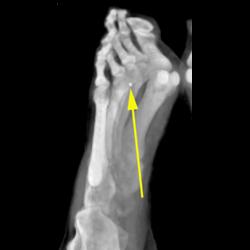

Diagnosis

Multiple Healing Rib Fractures